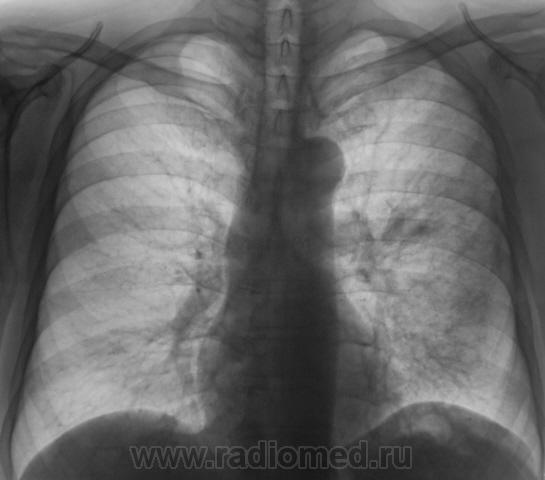

При расшифровке флюорограмм пациент "взят на контроль". Жалоб пациент не предъявляет. Подняли "архив", флюорограмма за 2009 г. - "норма".

Произвели стандартное дообследование.

Томограммы.